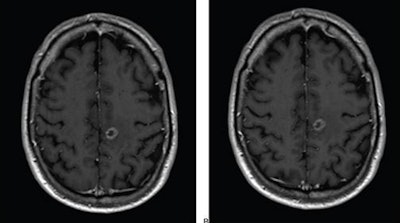

Axial T1-weighted MR images obtained using (A) standard-dose gadoterate and (B) reduced-dose gadobutrol four days later. Mean score across three readers for standard-dose gadoterate and reduced-dose gadobutrol was 3.4 and 3.4, respectively, for subjective lesion enhancement; 3.5 and 3.4, respectively, for lesion border delineation; and 2.9 and 2.9, respectively, for lesion internal morphology. Image and caption courtesy of the ARRS.The study included 141 patients with known or suspected central nervous system conditions who underwent contrast-enhanced brain MRI with standard-dose gadoterate (0.1 mmol/kg); if a lesion was found, the patients underwent a second MRI with reduced-dose gadobutrol (0.075 mmol/kg) within 15 days.

"Comparison of reduced-dose gadobutrol and standard-dose gadoterate versus unenhanced imaging demonstrated noninferiority using 20% margin for three primary efficacy measures: subjective lesion enhancement, lesion border delineation, lesion internal morphology," the ARRS said.